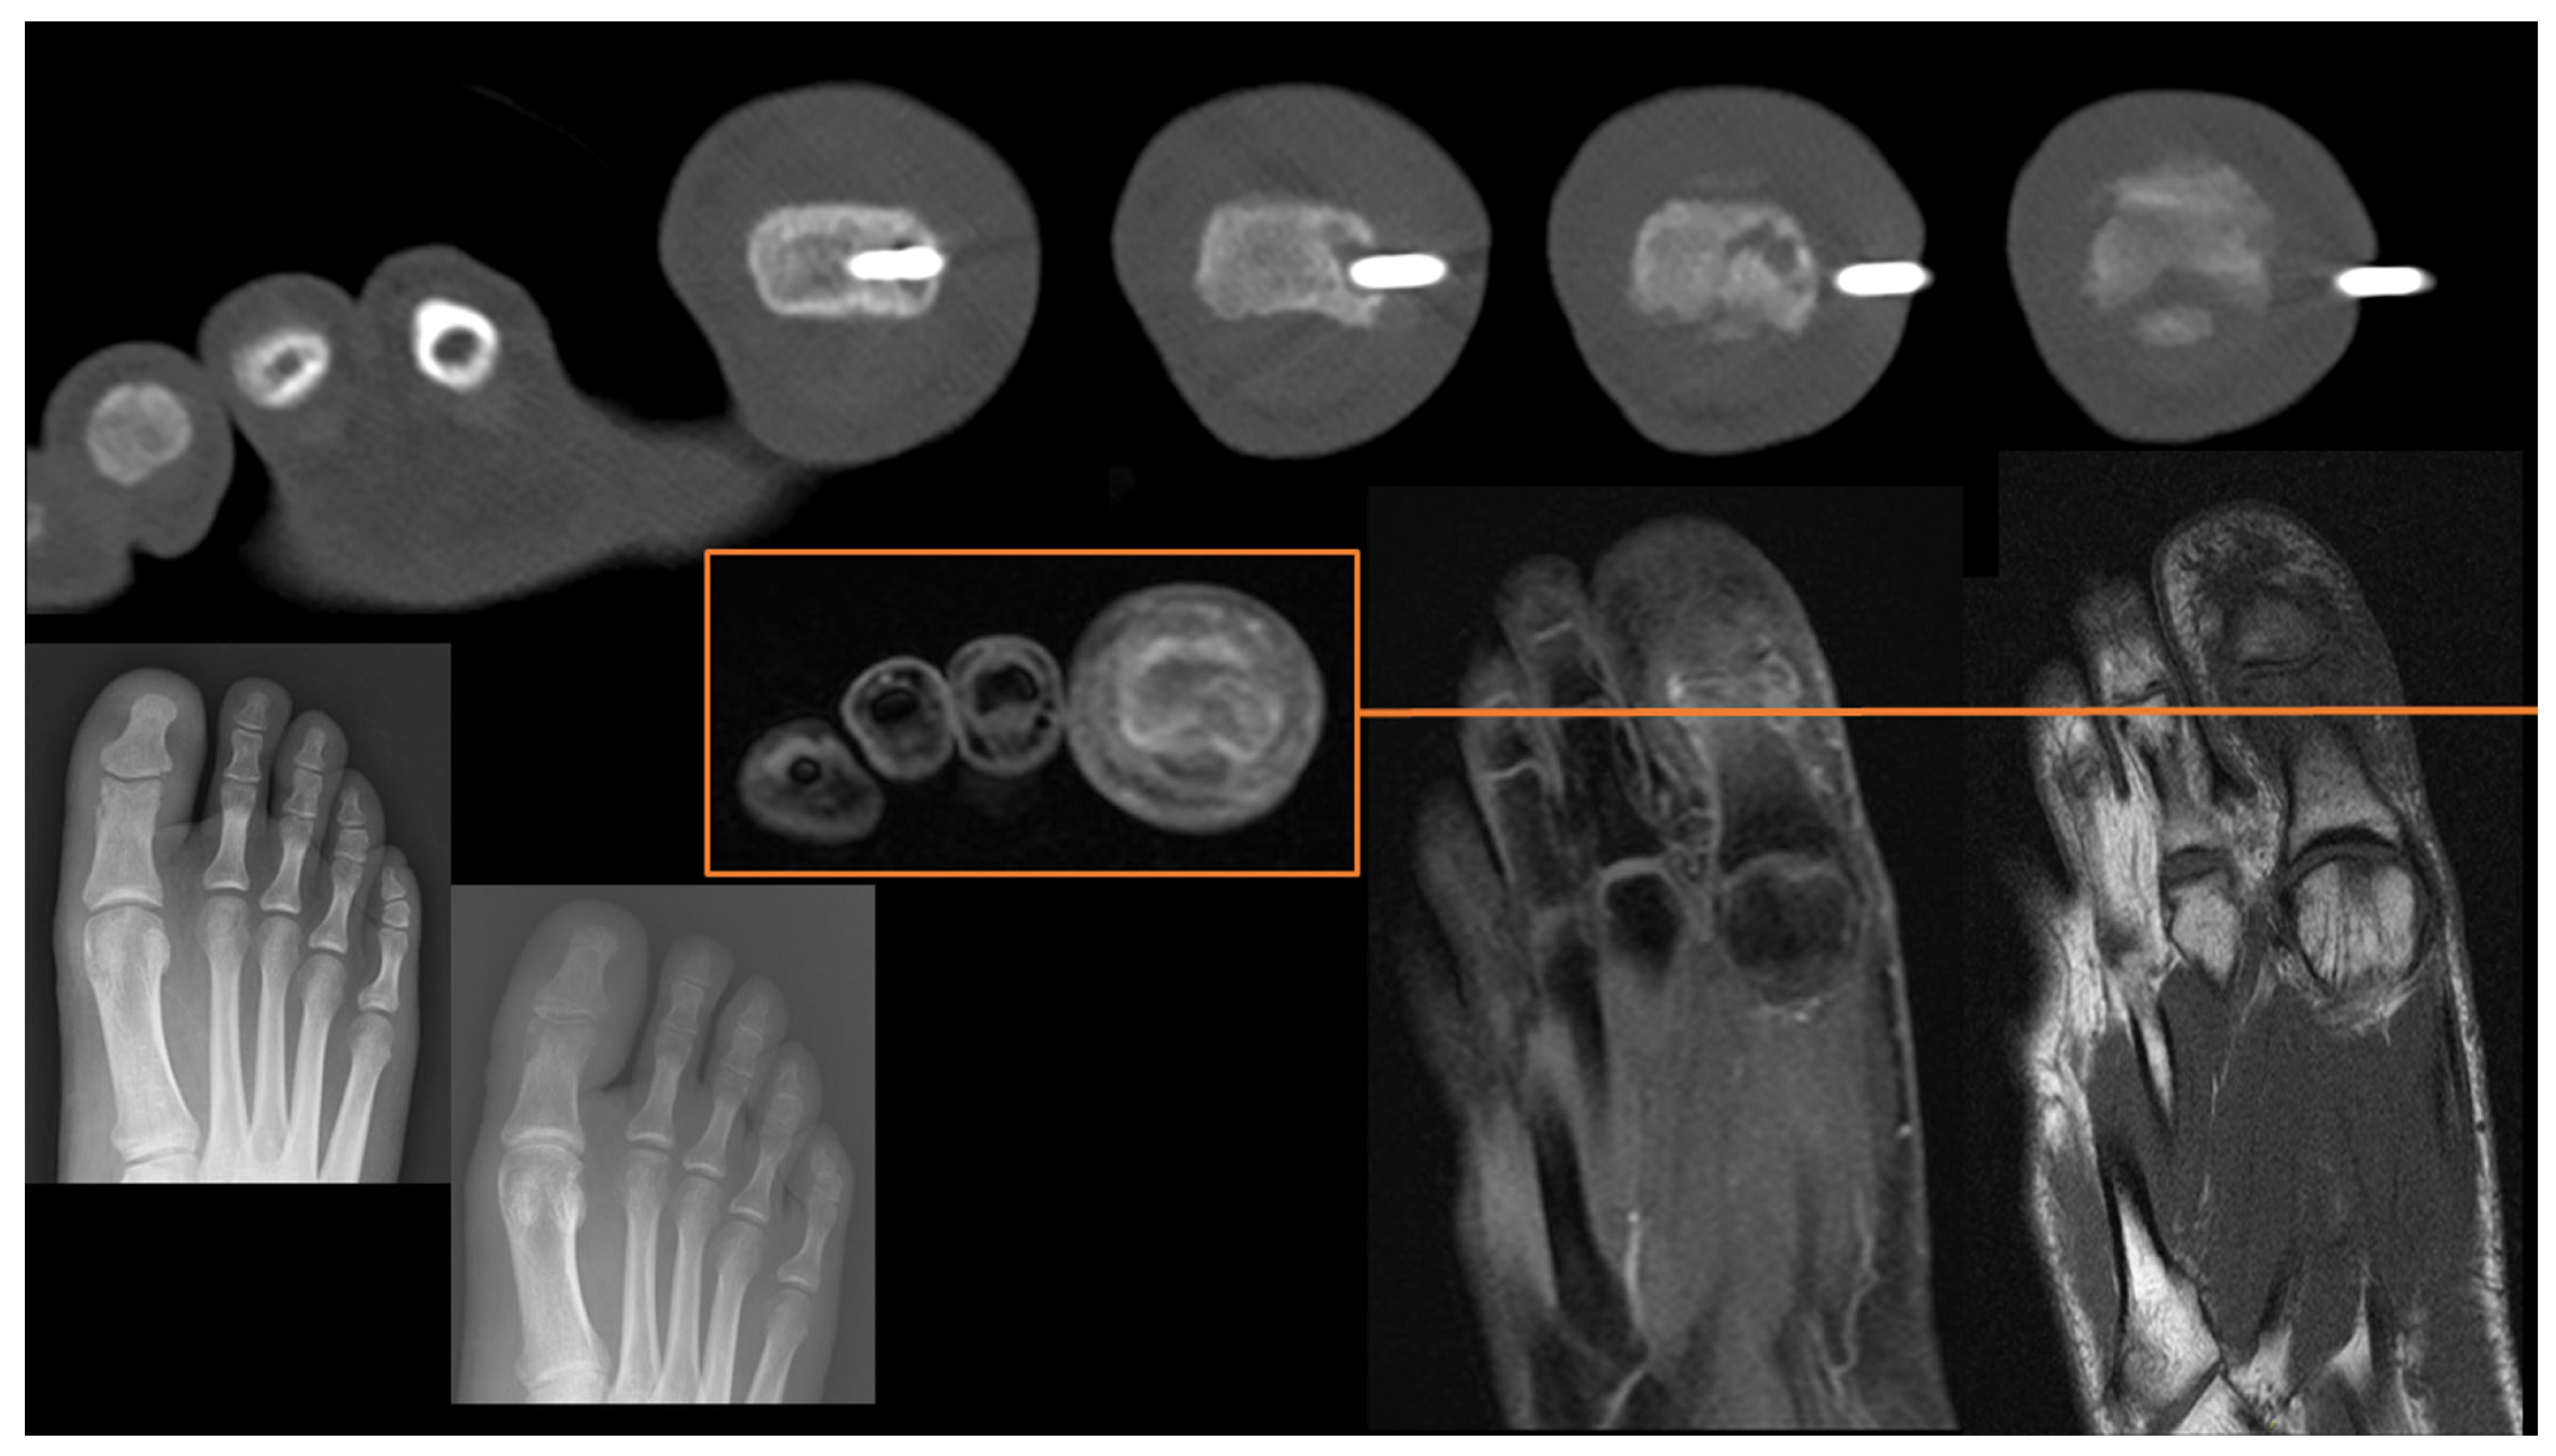

Hands and Feet

- Kim, W.; Sun, K.; Kung, J.W.; Wu, J.S. CT-Guided Core Needle Biopsy of Nonspinal Bone Lesions: Comparison of Occult and Visible Bone Lesions. Am. J. Roentgenol. 2023, 220, 104–114. [Google Scholar] [CrossRef] [PubMed]